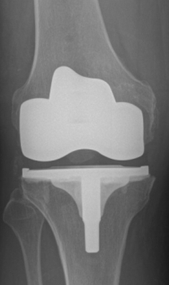

Wir halten ein großes Portfolio moderner und bewährter Prothesen vor, die sich entsprechend den o.g. Ausführungen vom Prothesendesign unterscheiden. Innerhalb des Designs liegen verschiedene Ausführungen und verschiedene Größen vor, so dass wir je nach Krankheitsbild für Sie eine individualisierte Versorgung anbieten können. Bei entsprechender Indikation kann der Kniegelenkersatz auch mit robotischer Unterstützung erfolgen, die Prinzipien werden in dem nachfolgenden Artikel aus FOCUS-Gesundheit 5/2023 verständlich dargestellt.

Sollte bei Ihnen eine Endoprothese in Frage kommen, wird durch Beurteilung verschiedener Faktoren der Prothesentyp aus dem o.g. Portfolio für Sie ausgesucht.